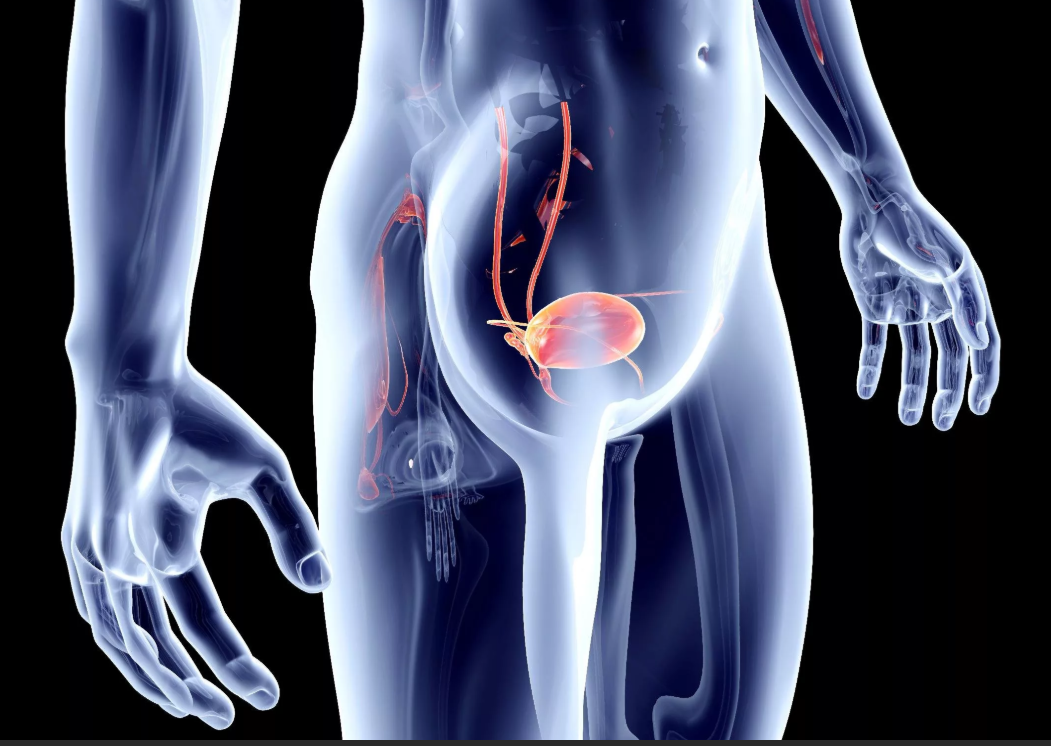

Рак мочевого пузыря у мужчин: симптомы на ранней стадии, что делать, прогнозы (сколько живут), лечение

У мужчин рак мочевого пузыря диагностируется гораздо чаще, чем у женщин. Как и у любого онкологического процесса, симптомы на ранней стадии практически отсутствуют и обнаруживается патология обычно поздно. Вопрос о том, что делать, консервативная или оперативная показана тактика лечения, во многом зависит от своевременной диагностики. Состояние больного и стадия развития опухоли определяет и прогнозы: сколько живут пациенты с таким диагнозом, зависит от нескольких составляющих.

Рак мочевого пузыря — это общий собирательный термин для обозначения онкологического процесса в определенном сегменте мочевыделительной системы. По частоте встречаемости всех заболеваний этого сегмента у мужчин, оно не относится к числу распространенных, хоть и имеет свое обозначении в МКБ 10.

Частота возникновения рака мочевого пузыря у мужчин вполне объяснима, если вспомнить, какие у него могут быть провоцирующие факторы, однако по мнению специалистов-онкологов, наибольшее значение имеет специфика устройства мочеполовой системы, значительно отличающейся от женской.